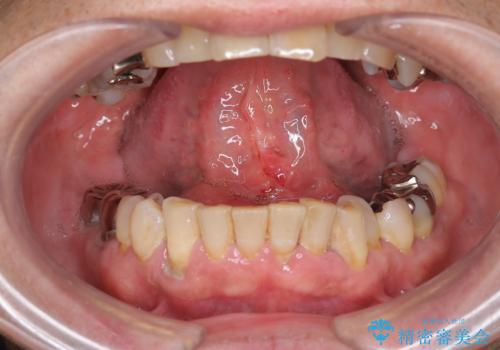

『舌小帯形成術』 ベロの動きを良くして滑舌を改善したい

- 舌の動きが制限され、滑舌を改善したい、と希望され来院されました。

舌小帯形成術を行うことで、滑舌の改善を図ります。形成術は約5分程度で終了し、1週間後に抜糸を行い治療は終了となります。

術後、舌の動きが改善され滑舌の改善を実感することができました。